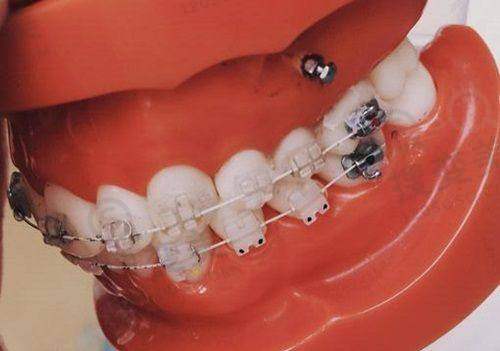

该医院设有多个口腔诊疗科室,像种植牙科、牙齿矫正科、口腔修复科、牙周病科等一应俱全。无论你是需要种植牙、矫正牙齿,还是进行口腔修复等,都能在这里找到对应的专精科室,满足不同患者的口腔健康需求。医院拥有一支经验多的医疗团队,他们凭借专精的知识和不错的技术,为患者提供高质量的口腔医疗服务。

医生团队方面,天津中诺口腔医院拥有一支经验多、技术娴熟的医生团队。种植科院长赵振宇是口腔医学硕士,从事口腔临床工作20余年,完成超过5000例种植手术,擅长立得用种植、即刻种植、即刻负重、半口/全口复杂种植、骨量不足种植等;正畸医生张少民从事口腔临床工作15年,专注于各类错颌畸形的矫治,擅长金属陶瓷矫正、隐形矫正、高难度颌面正畸技术;刘子豪医生是天津医 科 大学口腔医学博士,从事口腔临床工作多年,发表正规文章50余篇,其中SCI收录49篇,擅长全口、半口无牙颌种植、ALL - ON - 4、即刻负重技术、上颌窦内外提升术等。在收费价格上,种植牙国产的1980元起/颗,牙齿矫正传统金属托槽6800元起等,不过以上价格仅供参考,具体费用以就诊时医生诊断为准。患者对医院的评价也良好,特别多患者反馈种牙和矫正成效不错,尤其夸赞医生耐心技术好。

医院营业面积达4000平方米,是邯郸地区规模较大的私立口腔机构之一。院内设数字化种植中 心、正畸中 心、美学修复科等五大核心科室,并配备层流手术室与进口高端设备,如芬兰小牙片机、意大利Newtom CBCT机等,硬件条件达到精良水平。在特色技术方面,“立得用”种植体系在邯郸分院得到全方面应用。该技术通过3D数字化导板定位,实现微创种植、即刻负重,单颗种植仅需3 - 5分钟,半口或全口缺牙患者可当天完成种牙并修复咀嚼功能。医院还引进了精良的数字化美学矫正技术,结合DSD数字微笑设计,提升治疗精细度与美观度,无论是儿童还是成人,都能在这里找到适合自己的矫正方案。